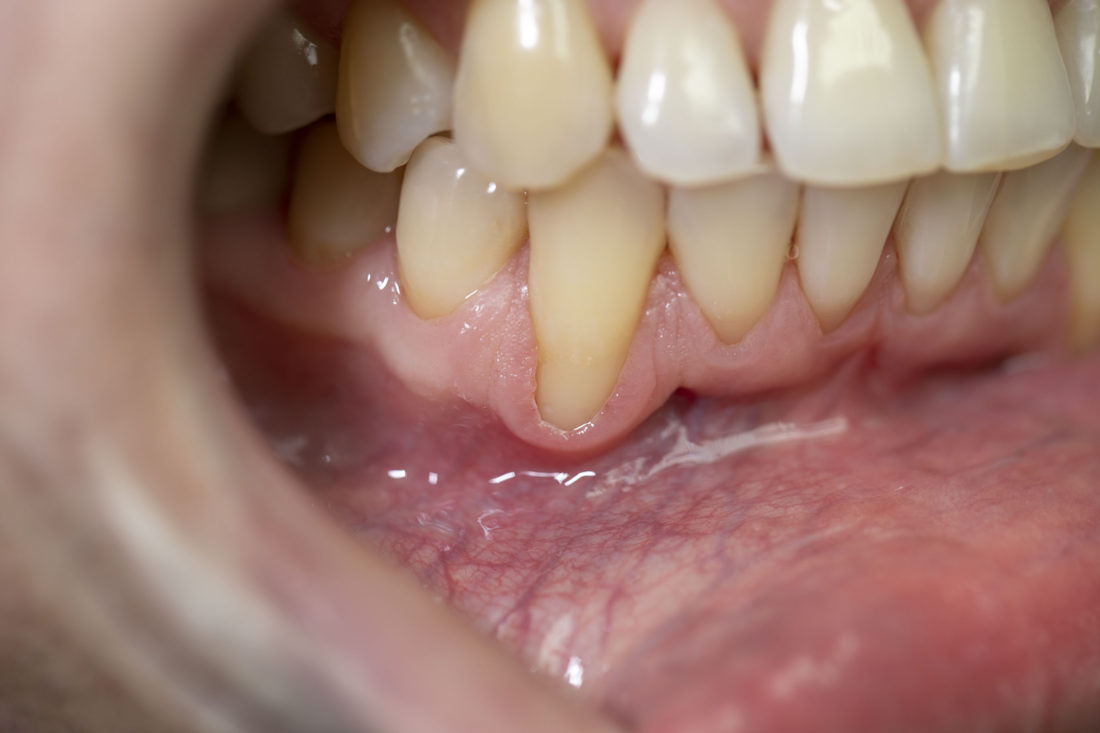

Результати наших робіт

• опущення ясен – поступова втрата, атрофія тканини. Рецесія ясен 3-4 ступеня супроводжується втратою міжзубної, кісткової тканини.

На фоні запущеного парадонтозу чи парадонтиту може розвинутись рецесія ясен. Також опущення ясен буває пов’язане з віковими змінами в організмі. До інших причин рецесії відносять індивідуальні особливості будови альвеолярного відростку, неправильне положення зубів, помилки при користуванні ортопедичними конструкціями, недостатню гігієну ротової порожнини.

• видиме опущення ясен та оголення зубних коренів, часто – прикореневий карієс.

Лікар насамперед проведе огляд та обстеження з використанням пародонтального зонда або мікроскопа для оцінки ступеня важкості рецесії. Легка рецесія ясен може лікуватися консервативним шляхом, за допомогою ін’єкцій колагену. Опущення ясен середнього та важкого ступеня є показанням до оперативного лікування (пластики). Пластичне закриття зони рецесії проводиться під місцевою анестезією. Зазвичай пересаджується клапоть сполучної тканини, взятої у самого пацієнта із зони ротової порожнини, багатої на колагенові волокна. У місці пересадки попередньо створюється кишеня чи тунель, куди вкладається трансплантат, після чого накладаються шви для з’єднання тканин. Тривалість та ціна операції залежить від кількості зубів, біля яких відбулося опущення ясен. Якщо рецесія ясен генералізована, тобто охоплює весь зубний ряд, операція може проводитись у кілька етапів.